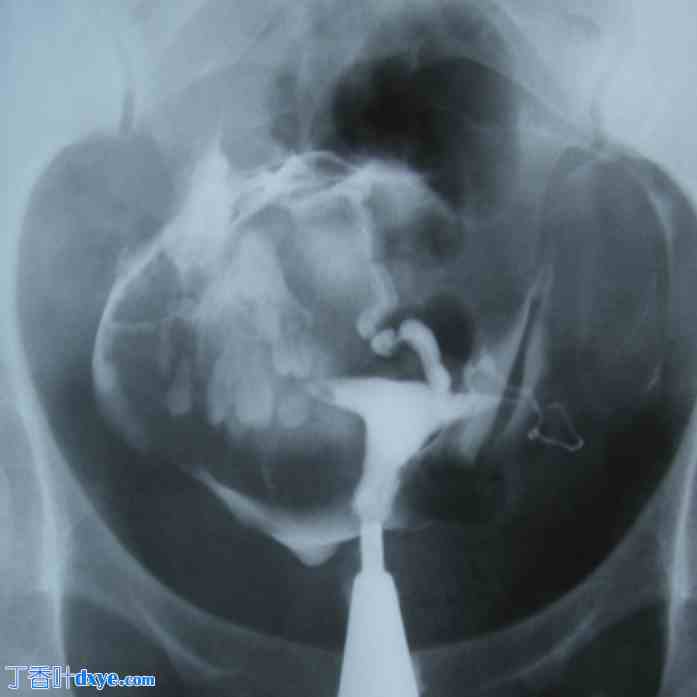

图 2。

30 岁继发性不孕女性的输卵管造影,宫腔正常。左侧输卵管末端有轻微积水。右侧输卵管因软组织肿块而移位。肿块内部可见多个牙齿结构外观的致密区域,代表大型皮样囊肿。